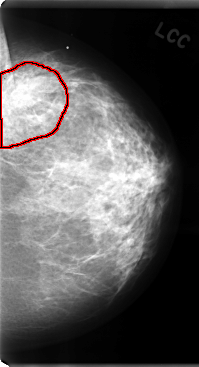

C_0080_1.LEFT_CC

FILE: C_0080_1.LEFT_CC.OVERLAY

TOTAL_ABNORMALITIES 1

ABNORMALITY 1

LESION_TYPE MASS SHAPE IRREGULAR MARGINS ILL_DEFINED

ASSESSMENT 4

SUBTLETY 4

PATHOLOGY MALIGNANT

TOTAL_OUTLINES 1

BOUNDARY